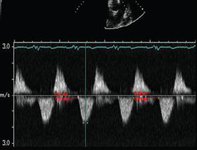

Doppler em um paciente com regurgitação pulmonar após reparo de tetralogia de Fallot. O paciente tem ventrículo direito restritivo e o Doppler mostra evidências de restrição com onda "A" anterógrada na artéria pulmonar

De: Chaturvedi RR, Redington AN. Heart. 2007 Jul;93(7):880-9; usado com permissão